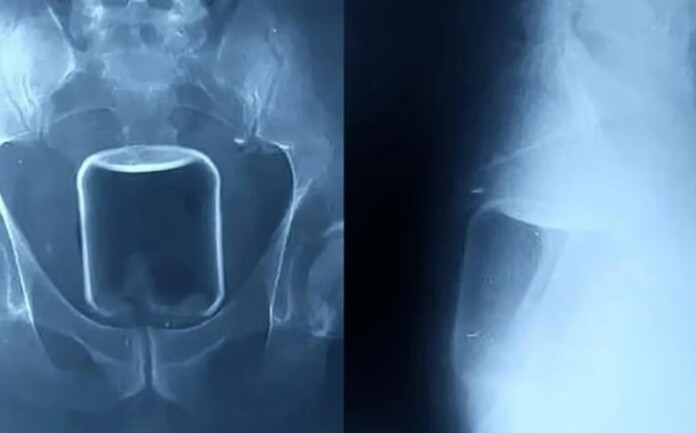

Os médicos alertaram que, se o copo tivesse se quebrado, ele poderia ter enfrentado hemorragias fatais ou danos irreversíveis a órgãos internos. Radiografias do paciente mostraram o copo alojado na parte superior do reto, avançando em direção ao intestino. Além do copo, os profissionais também removeram um preservativo e lubrificante, provavelmente utilizados durante o ato.